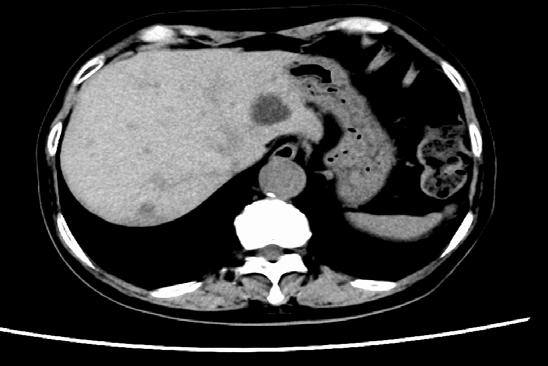

100 The Two Faces of Hepatocellular Carcinoma: Navigating Cancer Care and Liver Health

E Kaplan